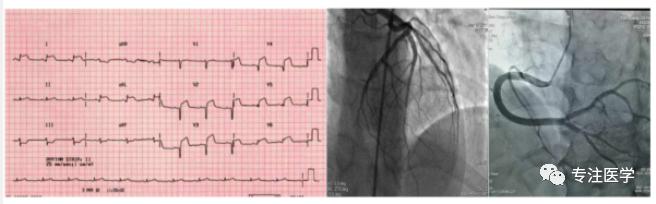

心电图呈急性心梗样改变,冠脉造影未见明显异常

AFM的早期诊治对预后至关重要。目前普遍认为其诊断依据为:在急性心肌炎发生基础上,短期内出现生命体征不稳定,需要应用正性肌力药、血管活*药性**和/或MCS治疗。然而,该诊断依据仍具有一定主观性:绝大多数患者在病情变化前未行EMB确诊为急性心肌炎;不同医生对病情严重程度的评估,以及使用相应药物和MCS治疗的时机有不同判断标准。因此,当临床出现不明原因的严重心脏表现、合并心肌坏死标记物cTN显著升高时应尽快排查AFM的存在:①前驱感染/药物接触史:病毒直接侵袭及其触发的心肌自身免损伤是急性心肌炎的重要发病机制;肠道病毒(如CVB)流感病毒(如HIN)、巨细胞病毒等嗜心肌病毒在AFM中较为常见;抗肿瘤的靶向药物(如PD-1)可诱发免疫性AFM、卡马西平等药物可诱发嗜酸性粒细胞增多性AFM。②CAG:出现类似急性心肌梗死表现时,尽快CAG检查有利于早期排除冠脉病变所造成的心肌坏死,立即采取针对AFM的抢救措施;对于儿童和青少年患者,如血流动力学不稳定, CAG/CTA则为病情缓解后的二线检查手段;③EMB与ILGE-cMR:EMB所提示的潜在病因及炎症细胞浸润类型对于AFM的诊断、针对性治疗和预后有重要价值,但只推荐应用于AFM疗效不佳、病因不明时: LGE-cMR也是诊断急性心肌炎的重要方法( Lake-louise标准),适用于AFM病情相对稳定后进行,尤其是未行EMB检查者,但它不能取代EMIB在心肌炎诊断中的地位。④注意与合并有多器官衰竭的脓毒血症性心肌炎、感染性休克等相鉴别。